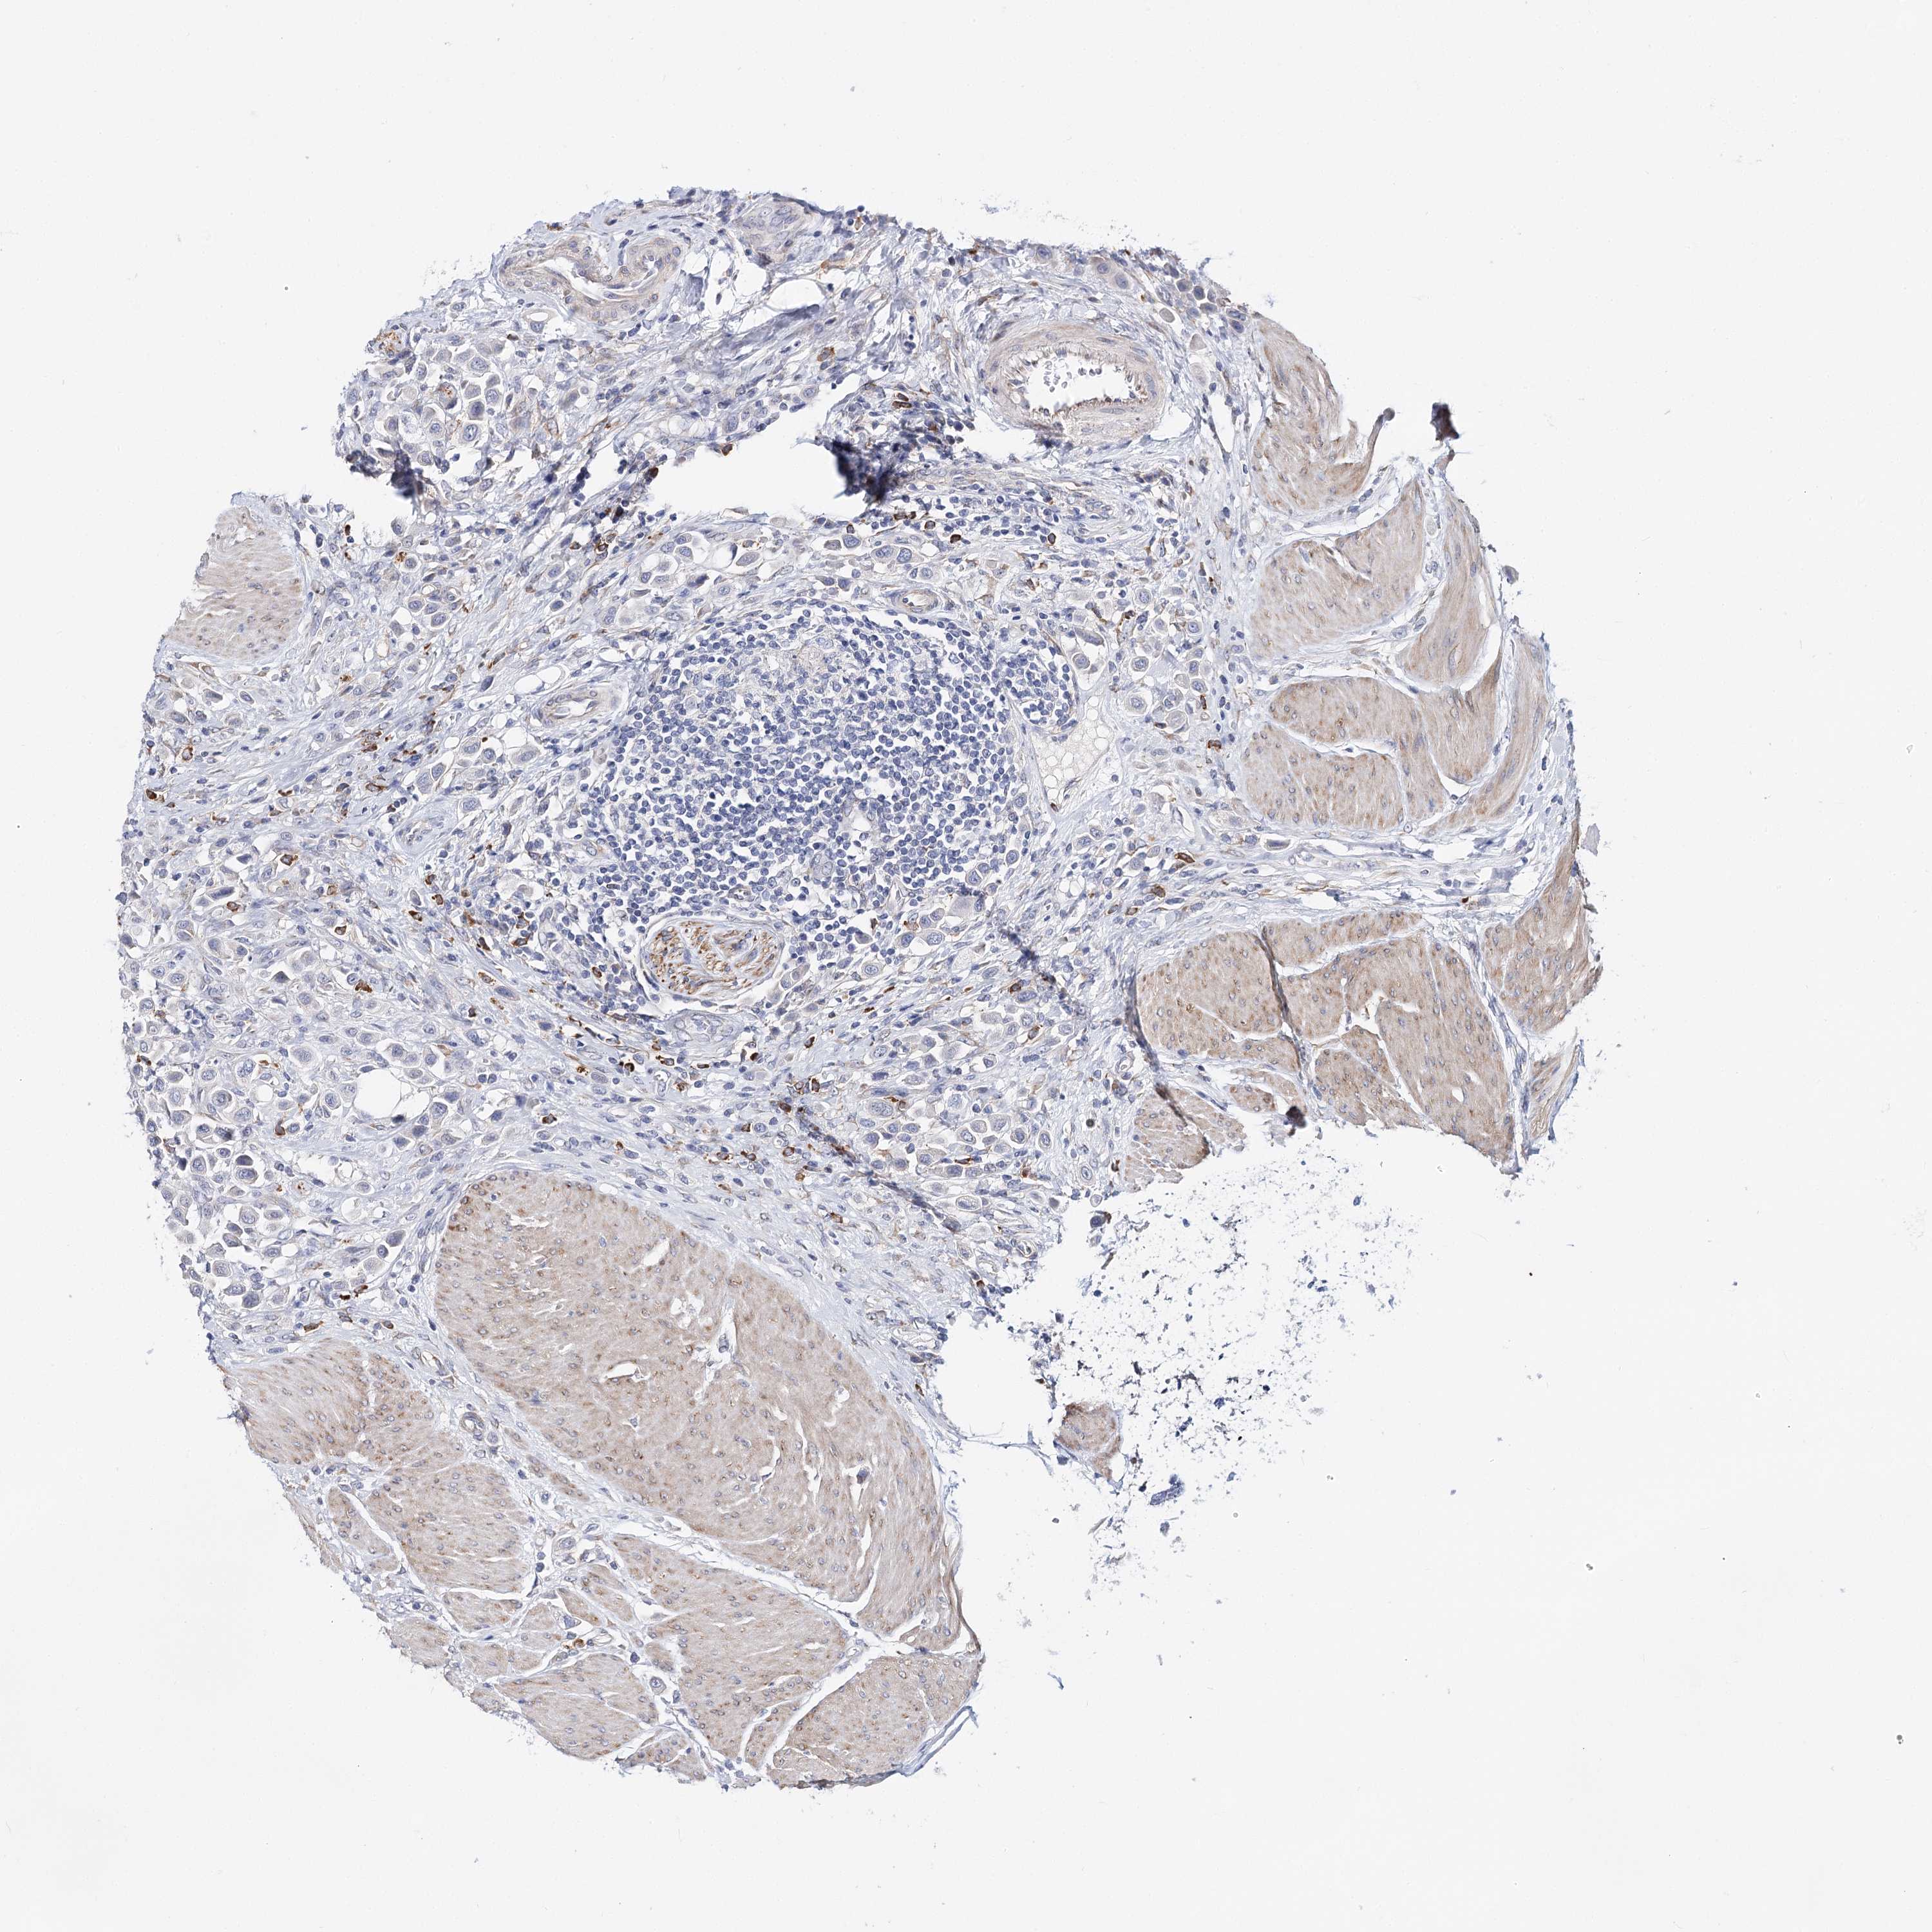

UROTHELIAL CANCER - Protein expressioni

A mouse-over function shows sample information and annotation data. Click on an image to view it in a full screen mode. Samples can be filtered based on level of antibody staining by selecting one or several of the following categories: high, medium, low and not detected. The assay and annotation is described here.

Note that samples used for immunohistochemistry by the Human Protein Atlas do not correspond to samples in the TCGA dataset.

Antibody stainingi

Antibody staining in the annotated cell types in the current human tissue is reported as not detected, low, medium, or high, based on conventional immunohistochemistry profiling in selected tissues. This score is based on the combination of the staining intensity and fraction of stained cells.

Each image is clickable and will lead to virtual microscopy that enables deeper exploration of all samples and also displays staining intensity scores, fraction scores and subcellular localization as well as patient and tissue information for each sample.

Antibody HPA038289

Antibody HPA038290

Staining

High

Medium

Low

Not detected

Intensity

Strong

Moderate

Weak

Negative

Quantity

>75%

75%-25%

<25%

None

Location

Nuclear

Cytoplasmic/membranous

Cytoplasmic/membranous,nuclear

Urothelial carcinoma, High grade